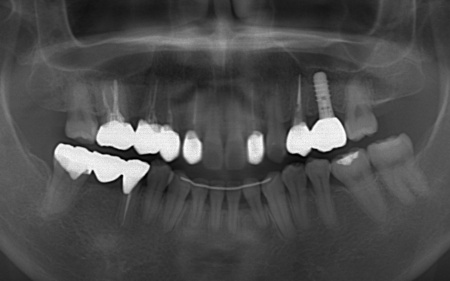

40代女性 矯正治療で噛み合わせを整えたあとセラミックの被せ物・詰め物で修復した症例

拝見したところ、左下と右上の歯はともに大きな虫歯があり、歯だけでなく被せ物を支える土台の部分にも影響が及んでいました。

さらに、ほかの歯に入っている詰め物や被せ物の周囲にも、過去に治療した部分に再び虫歯ができる二次カリエスが複数見つかりました。

また、噛み合わせを確認したところ、奥歯で噛み合わせた際に上下の前歯が当たらず隙間ができる開咬(かいこう)が認められました。

なお、左上の奥歯には人工歯根を埋め込んで失った歯を補うインプラントが装着されていたものの、人工歯根の位置や骨との結合状態に問題はありませんでした。

そのため、人工歯根部分はそのまま活用し上部に装着する人工歯のみを新しく作製しています。